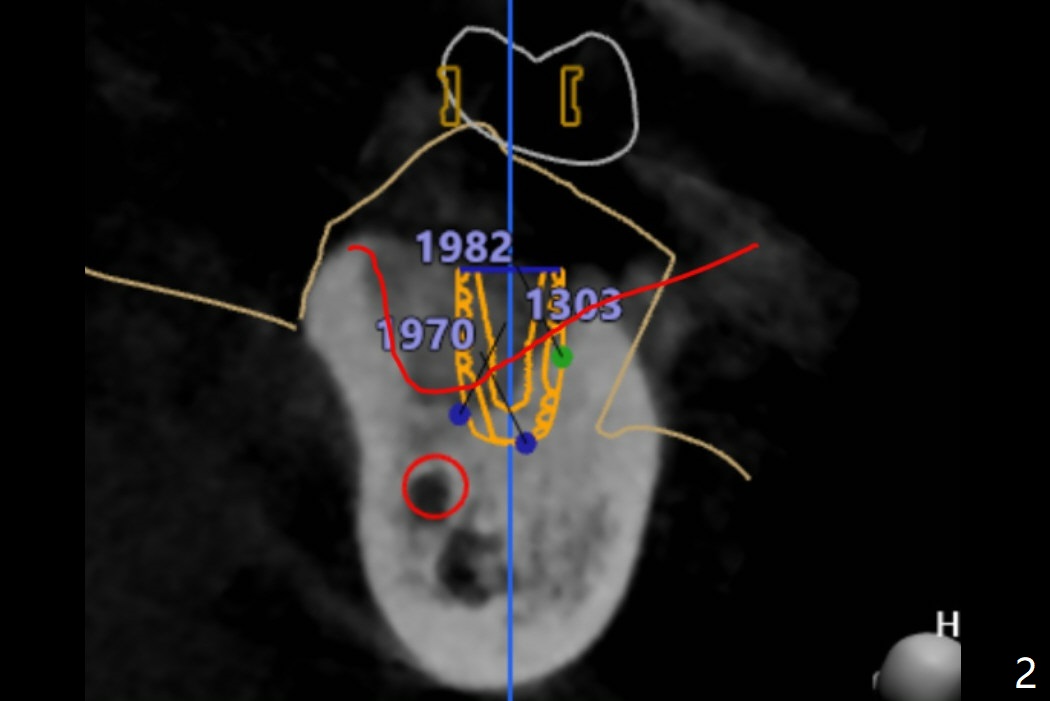

It is always my pleasure to hear back from you.  I have reviewed the planning of Ms. Pan's case again and I think this picture would help you understand the reason why (Fig.2).

When you look at the bottom part divided by the red line. It is very dense bone. However when I looked at the upper part from the red line even it showed high HU around 1000, but still as it is grafted bone, it may have not had the actual fixing stability at the top. That's why you might have felt that tapping which goes down 3mm at the top for the cortical bone has low resistance.  However, those white dense part at the apex helped to hold the implant firmly to achieve the torque.

And let's not tap it for the grafted area. I see the same bone density but the different contrasts on the CT data. So I will make sure to include that on the sequence next time. For the distalized position, I don't think it is distalized that much because it is good to have at least 2-3mm distance between implant to the nature root. I've measure it and it was 2.83mm in between (Fig.8). But we can make this space narrower if you want.